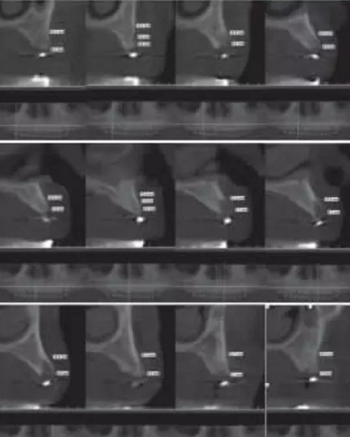

1.2.3治療過程:先行微創(chuàng)拔除14、13、21、22、23、24及25,搔刮拔牙窩去除炎癥組織,常規(guī)制作一副上頜過渡義齒(圖4,5)。2個(gè)月拔牙術(shù)后復(fù)診,利用上頜過渡義齒作為個(gè)性化托盤取上頜模型并翻制石膏模型,在石膏模型上根據(jù)過渡義齒標(biāo)出各個(gè)牙位,同時(shí)利用壓膜機(jī)制作放射性模板(如圖6)?;颊吲宕鞣派湫阅0迮臄z全景片及CBCT(如圖7、8)。

圖8 佩戴放射性模板CBCT

放射性模板是指帶有放射性阻射標(biāo)記物的模板,在患者種植手術(shù)前戴入口內(nèi)并進(jìn)行放射性拍攝,可評估種植位點(diǎn)骨質(zhì)及可用骨量,從而設(shè)計(jì)種植體的數(shù)目、位點(diǎn)及方向,指導(dǎo)最終手術(shù)方案。放射性模板能顯示種植位點(diǎn)或未來修復(fù)體的信息,它的組織面需與其下方的粘膜緊密貼合且在放射性拍攝過程中保持穩(wěn)定位置。本病例首先按照全口修復(fù)計(jì)劃,給患者制作上頜過渡義齒。利用過渡義齒作為個(gè)性化托盤取模翻制石膏模型,并在石膏模型上按照過渡義齒標(biāo)記牙位,繼而使用真空壓膜機(jī)制作樹脂薄膜導(dǎo)板,然后在樹脂導(dǎo)板相應(yīng)牙位打孔并填塞放射性顯影的材料如牙膠?;颊吲鍘Х派湫阅0暹M(jìn)行錐形束CT(CBCT)的掃描,從而得到種植位點(diǎn)骨組織的情況。牙列缺失的患者其放射性模板由粘膜支持,有可能在放射性掃描的過程中移位,可使用咬合記錄進(jìn)行固定。本病例所制作的放射性模板與患者的粘膜較為貼合,有較強(qiáng)的固位力。